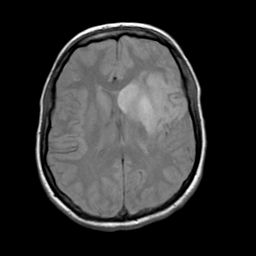

Acute Stroke: proton density-weighted MR -- Slice #15

[Home][Help][Clinical][Tour 1] Slice 15